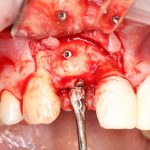

Для получения костного блока, мы открываем донорскую зону, наружную косую линию нижней челюсти.

Получение костного аутотрансплантата.

Здесь потребуется пародонтологический зонд с миллиметровой разметкой или какой-то другой измерительный прибор (операционная линейка). Ранее по КЛКТ я измерил костный дефект, теперь нужно нанести границы будущего костного блока на донорскую зону.

Для получения костного блока мы использовали ультразвуковую пьезохирургическую систему. Это самый удобный и безопасный инструмент для проведения подобных манипуляций. С помощью него мы сформировали и выделили костный блок. Он должен отделяться легким движением остеотома или элеватора. Как это сделать правильно — читай здесь>>

Я зафиксировал костный блок практически без адаптации на несколько винтов. Обрати внимание, что винты находятся в зоне, где не планируется установка имплантатов. Фиксация должна быть надежной, поскольку мне еще предстояла подготовка лунок для имплантатов. Трех винтов для этого вполне достаточно.